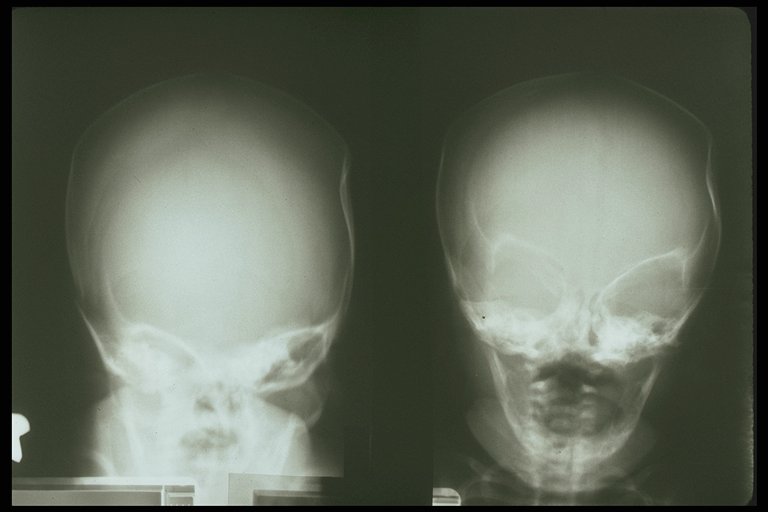

Depressed skull fracture caused by birth trauma

TPeriosteal reaction of skull is demonstrated in skull injury